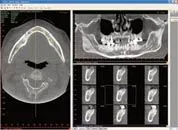

i-CAT 's Unparalleled, 3-D Imaging Technology

The Leader in Cone Beam 3-D Dental Imaging Introduces the Most Complete 3-D Imaging System for Quicker and More Comprehensive Diagnostic Treatment Planning.

Building on i-CAT's unparalleled, 3-D imaging technology - the next generation i-CAT® offers a new ergonomic design, groundbreaking performance advancements and a wealth of new and improved features.

Low Radiation Dose

Best image quality with less radiation to the patient ½ the Dose of a Full Mouth Series NEW Low dose settings for follow-up scans and children 35-136 uSv (estimated, actual dosimetry results expected in the near future).